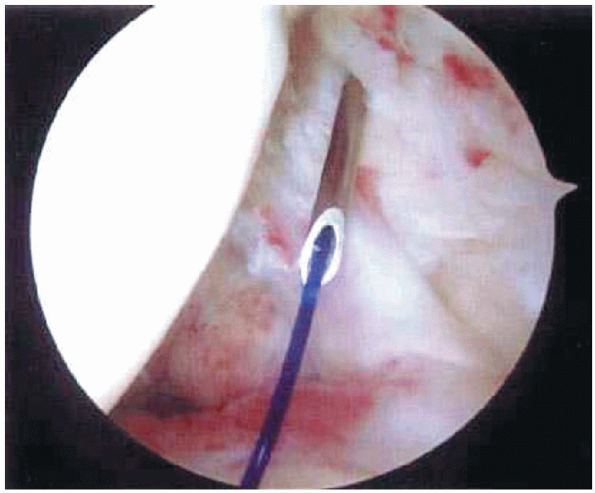

carefully inspected and partialor full-thickness tears are identified (Fig. 2-10). A

suture marker can be used to better assess the extent of a tear. A

monofilament suture is placed through a spinal needle passed

percutaneously across the area in question (Fig. 2-11).

![]() |

|

FIGURE 2-10.

Arthroscopic view of the rotator cuff tear. This tear is located just posterior to the biceps tendon at the insertion of the supraspinatus. |